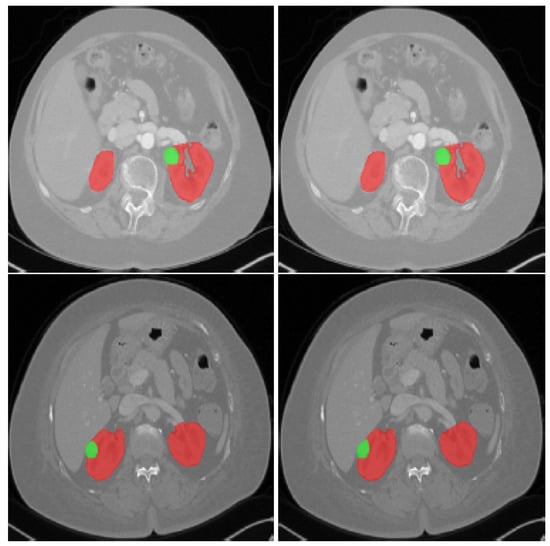

4.1. Renal Imaging